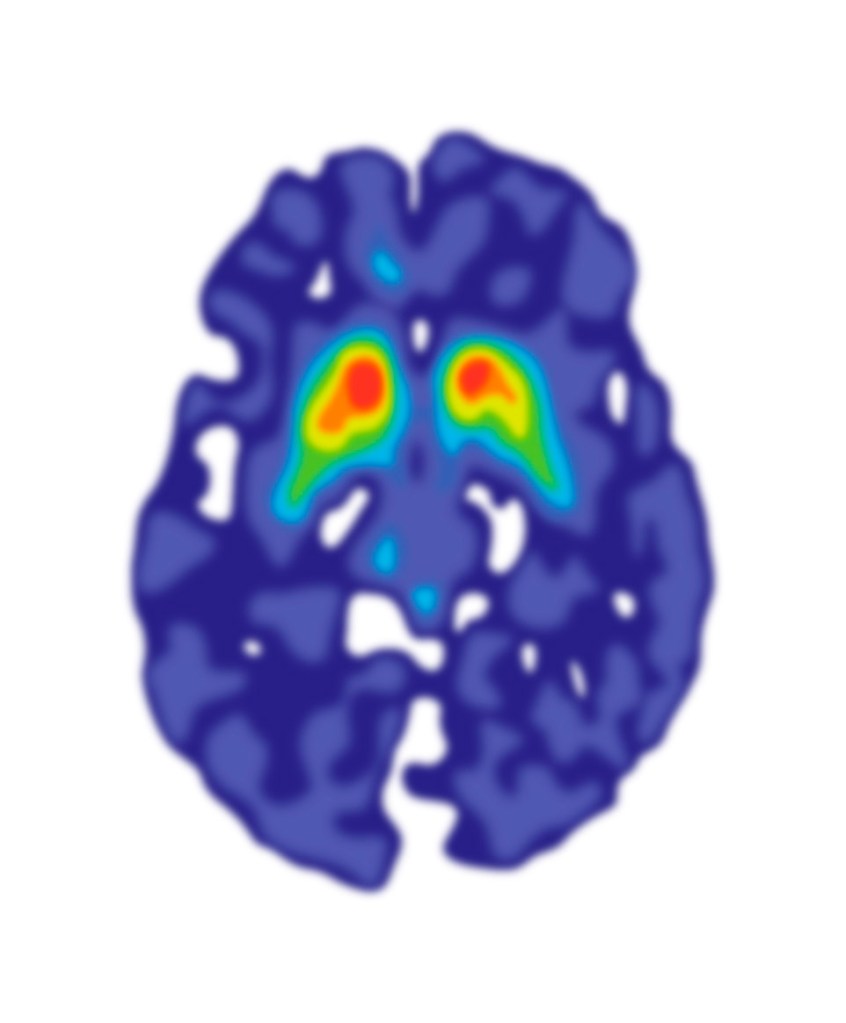

Following the meeting with Giovanna to review the first version of the FDOPA PET Imaging leaflet, Gill worked on the revisions needed to create the second version. Giovanna had provided three different photographic images of PET scans:

Gill experimented with drawing the rainbow colour-scheme and the blue-green colour scheme PET scans, as the red colour scheme is not as visually appealing and would not work as well with the existing illustrations. The scans will have to be placed on a black background (as in the header image of this post) to look their best, and to match how the scan results appear in the PET imaging software.

Gill then revised the text to even out the line lengths and adjust spacings. As the PET scans require a black background, Gill extended that down from the title bar. This black are does help to separate the first two sections of the text from the third section, although the layout will probably need more work. Gill added the blue-green PET scan illustrations, although the colours can be changed – it may be worth including some red to tie-in with the KCL logo and the elapsed time image. She also added the blue-green PET scan images to the screens in the radiographer illustration.